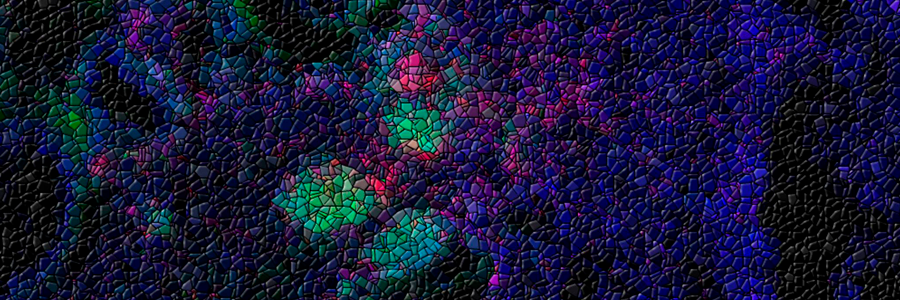

The image shows mouse lung (blue) 14 days after influenza A infection with ectopic lymphoid structures identified by the presence of high numbers of B cells (in green) and T cells (in pink). The mosaic effect is a digital modification. Credit: Dr Alice Denton, Babraham Institute.

The researchers found that germinal centre formation in the lungs is initiated via cascade of events, whereby a chemical message (type I interferon) produced by lung cells in response to infection triggers the production of a chemical attractant – a ‘come here’ flag to the immune system. In response to this signal, B cells (the immune cells that produce antibodies) are recruited to the lungs and initiate the formation of germinal centres. These lung-based germinal centres produce a different repertoire of B cells; ones that produce more broadly reactive antibodies providing cross-protection across different influenza strains.